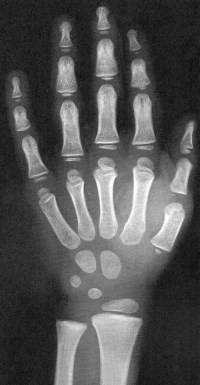

Sexo Masculino

Recém-Nascido

idade óssea - RN